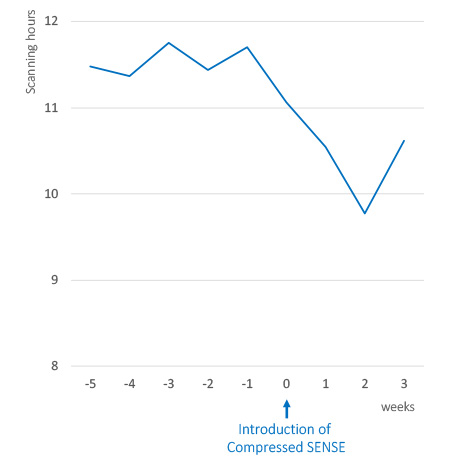

残業時間の削減

1日あたりの検査スループットを維持しながら残業時間を削減します。

放射線科領域において、MR検査の予約が埋まっているという状況はよくあります。これは、通常の業務時間を過ぎても検査が続き、スタッフが残業せざるを得ない状況をつくります。Compressed SENSEを使用すると、MR検査の時間が短縮され、スケジュール管理が容易になり、患者だけでなくMR担当者の業務負担を減らすことができます。

Compressed SENSEがもたらす検査時間の短縮と柔軟なスケジュール管理により、スタッフの残業時間が削減できます。1

残業時間の削減、患者スループットの維持

オーストリアのCTI Innsbruckでは、Compressed SENSEの導入完了後、1日あたりの検査スループットを維持しながら、スタッフの残業時間を1時間以上削減しました。

Compressed SENSEを使用してスキャン時間を短縮し、過密な業務スケジュールによるMRスタッフのストレスも緩和されました」

熊代正行博士、放射線技師および放射線技師長、倉敷中央病院